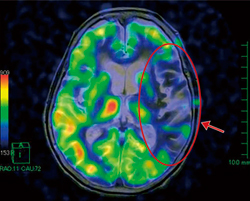

脳腫瘍や脳卒中などの虚血性疾患においてASLの有用性は高いが,位置関係の把握が困難な場合も見受けられる。そこでASLデータ中のperfusion imageデータとT2強調画像をfusionさせることにより,位置関係をより正確に描出することが可能である(図1〜4)。

図1 頭部MRI 3D T1強調画像とperfusion imageのfusion画像:三叉神経鞘腫症例

図3 頭部MRI T2強調画像とperfusion imageのfusion画像:脳梗塞症例 |

図4 頭部MRA:脳梗塞症例(図3と同一症例) |